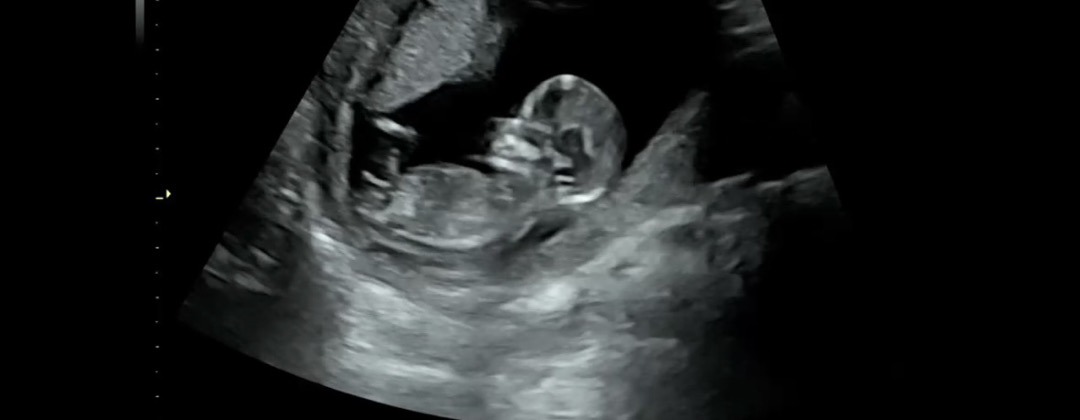

12주 1일차) 성별 예측 가능할까요~?

오늘 병원 다녀왔는데 넘궁금해요!!